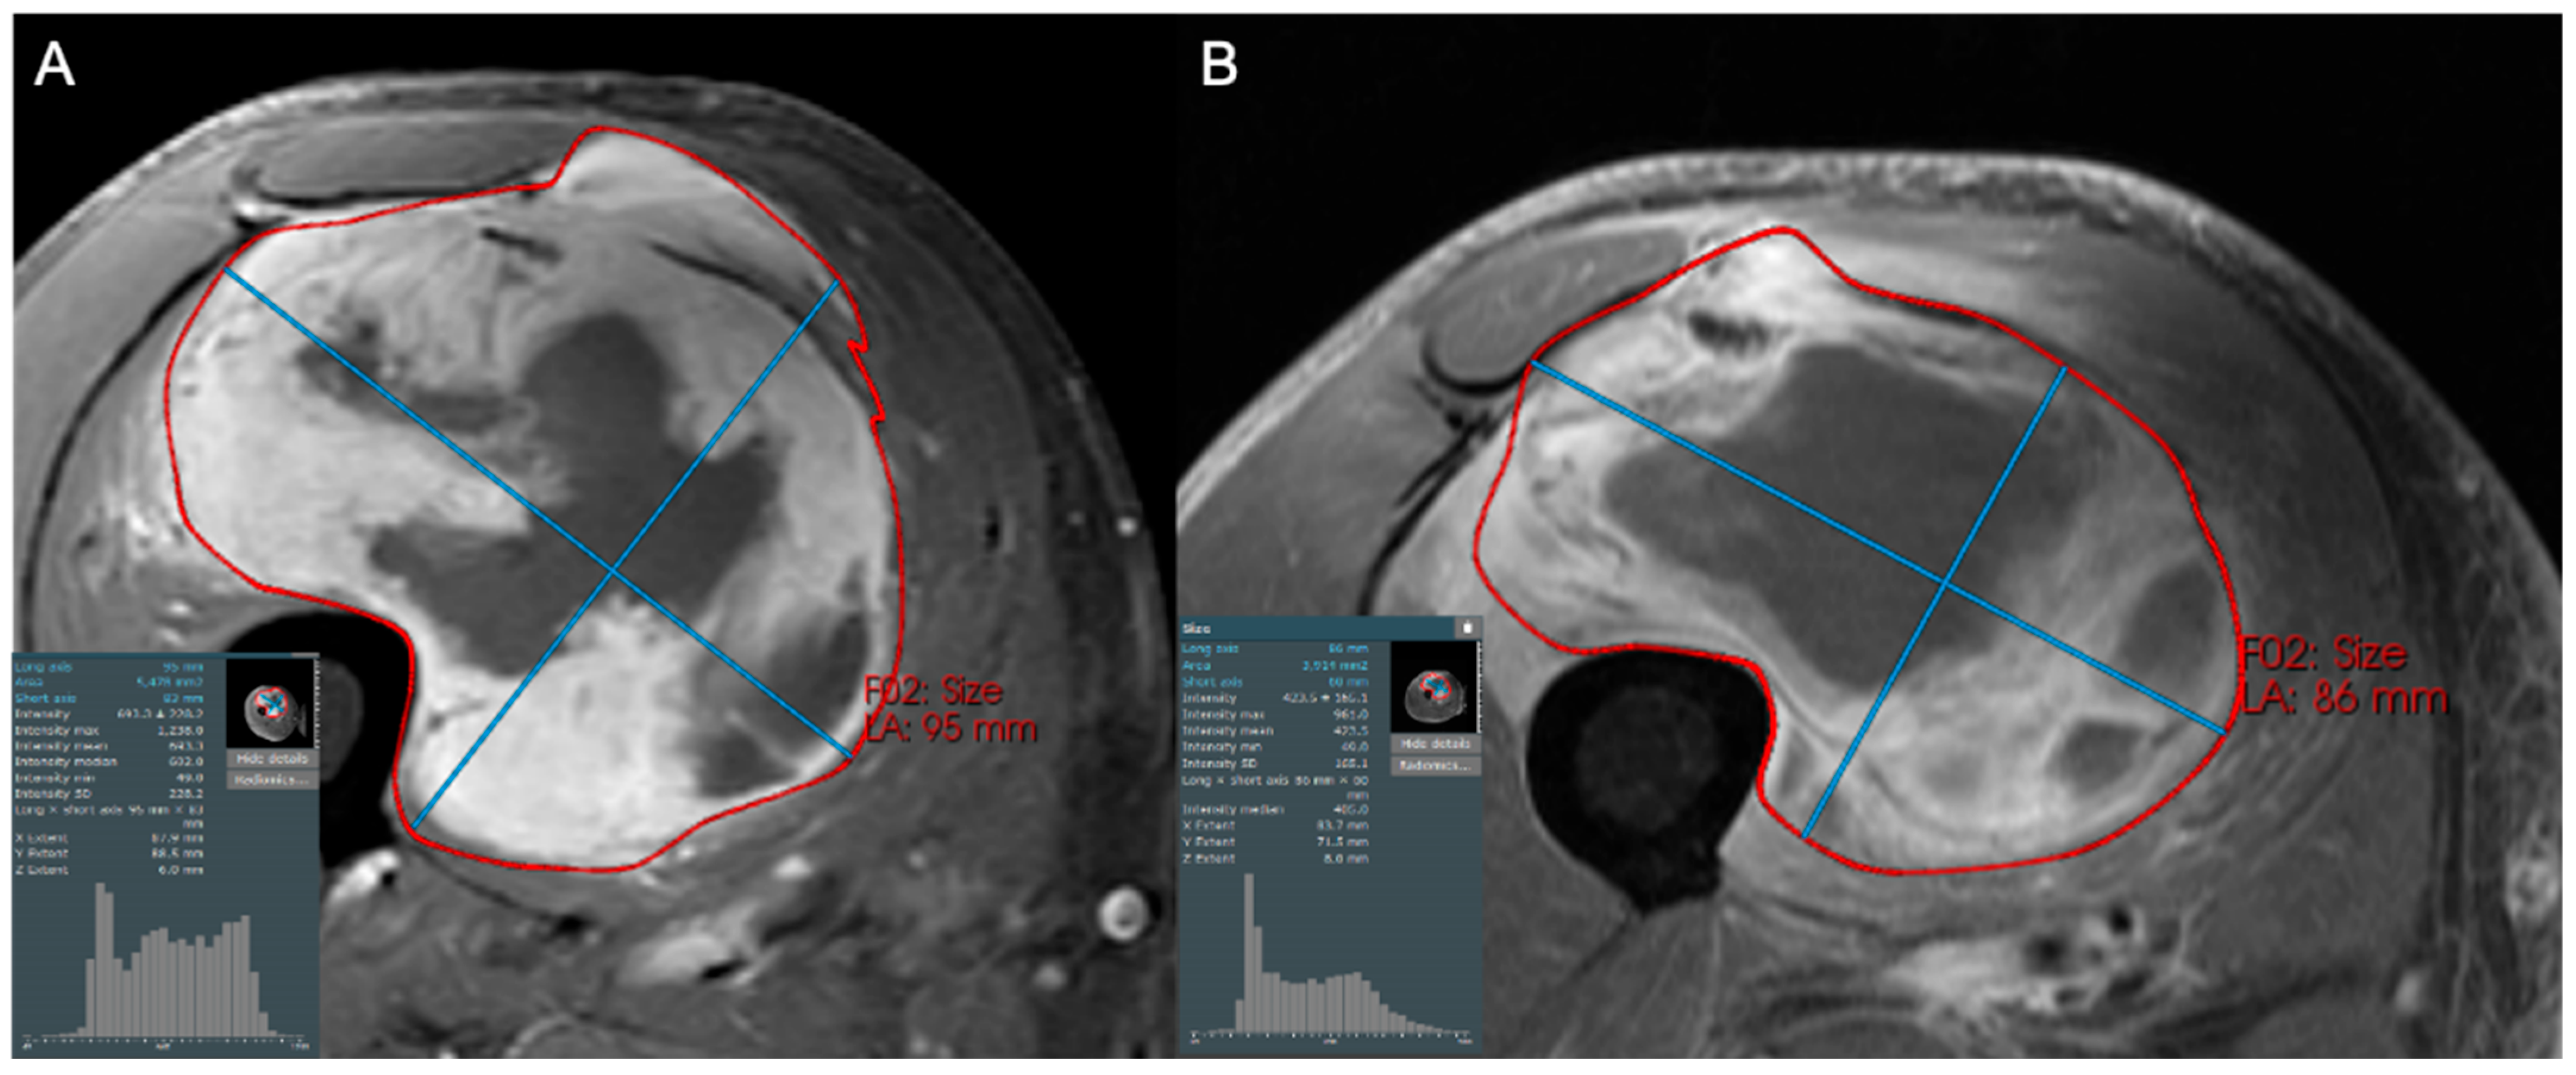

- Subhawong, T.K.; Feister, K.; Sweet, K.; Alperin, N.; Kwon, D.; Rosenberg, A.; Trent, J.; Wilky, B.A. MRI Volumetrics and Image Texture Analysis in Assessing Systemic Treatment Response in Extra-Abdominal Desmoid Fibromatosis. Radiol. Imaging Cancer 2021, 3, e210016. [Google Scholar] [CrossRef]

- Singer, A.D.; Pattany, P.M.; Fayad, L.M.; Tresley, J.; Subhawong, T.K. Volumetric segmentation of ADC maps and utility of standard deviation as measure of tumor heterogeneity in soft tissue tumors. Clin. Imaging 2016, 40, 386–391. [Google Scholar] [CrossRef]